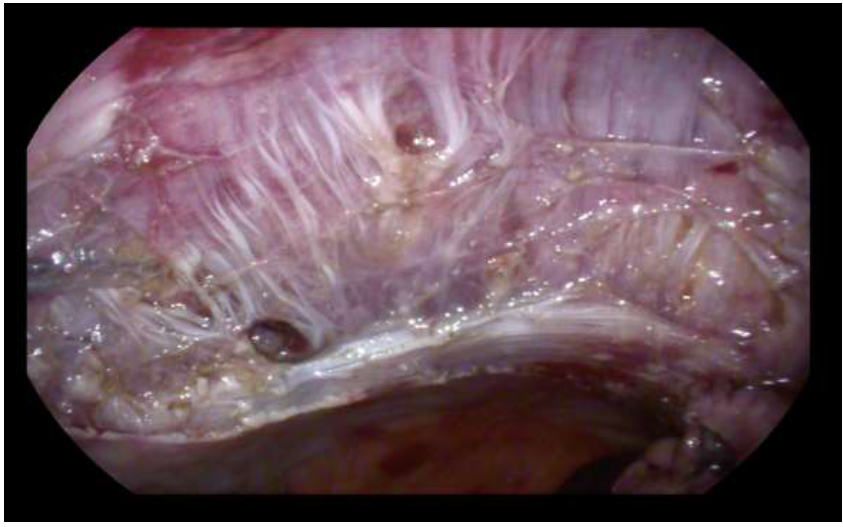

Here we report the case of a 77-year-old ASA 2 woman, who underwent to colonoscopy for sideropenic anemia and positive FIT. Examination showed a rectal granular nodular-mixed laterally spreading tumor (GM-LST) with a dominant nodule of 5 cm and a psudodepressed central area [figure 1,2]. The lesion was extended on the two third of rectal circumference involving the second and the third Huston fold and was judged suspected for invasive carcinoma. The histological examination reported low and high-grade dys-plasia. At total body computed tomography (CT)  no metastatic lesion was detected. Pelvic magnetic reso-nance (MRI) was consistent with T2N0, showing the extension of the lesion nearby the muscularis propria, without a clear distinction plane. In addition, a rectal endoscopic ultrasound (EUS) was requested, confirm-ing the MRI findings. Given the well-known risk of EUS and MRI overstating, as reported by recently re-leased ESGE guidelines [4] and after a gastrointestinal multidisciplinary team (MDT) discussion, the pa-tient was proposed for endoscopic submucosal dissection4. For the procedure, we used a standard   diag-nostic Pentax gastroscope  mounted with a conic distal end cap (ST Hoods, Fujifilm®). First, a mucosal incision was made approximately 5mm around either the proximal and distal side of the rectal lesion, fol-lowed by submucosal dissection using DualKnife J 1.5mm (Olympus®). During the dissection, a deeper submucosal invasion was suspected  beneath  the dominant sessile nodule, where the submucosal space was progressively disappearing for muscular retraction and also for fibrotic reaction [Figure 3]. In this area we moved to the inner circular muscular layer dissection, even using the same small tip knife. The dissec-tion was completed using the Hook Knife J (Olympus) for the lateral part, resulting in complete resection of the lesion, 10x6 cm in size [Figure 4]. The resection phase took 90 min. Hemostasis  was achieved with monopolar  forceps (Coagrasper - Olympus®). The base was sutured using through-the-scope clips and a hemostatic matrix (Purastat®, 3ml) was apposed  to prevent delayed bleeding. Precautionary, the patient was hospitalized for three days and then discharged after uneventful observation. Histological examination of the lesion reported well-differentiated adenocarcinoma (G1) focus over a high-grade dysplasia tubulovil-lous adenoma, no tumoral budding or vascular invasion, absence of tumor on the resection plane and sub-mucosal invasion limited to 500 μm. Histopatology also showed the circular muscular layer on the resection plane of the lesion  [Figure 5]. MDT indication was endoscopic follow-up after 6 months.

Figure 3